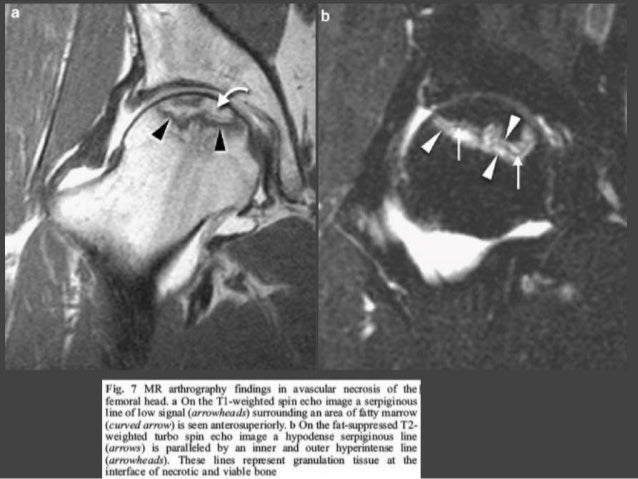

Степени аваскулярного некроза

Степени аваскулярного некроза 116 фотографий